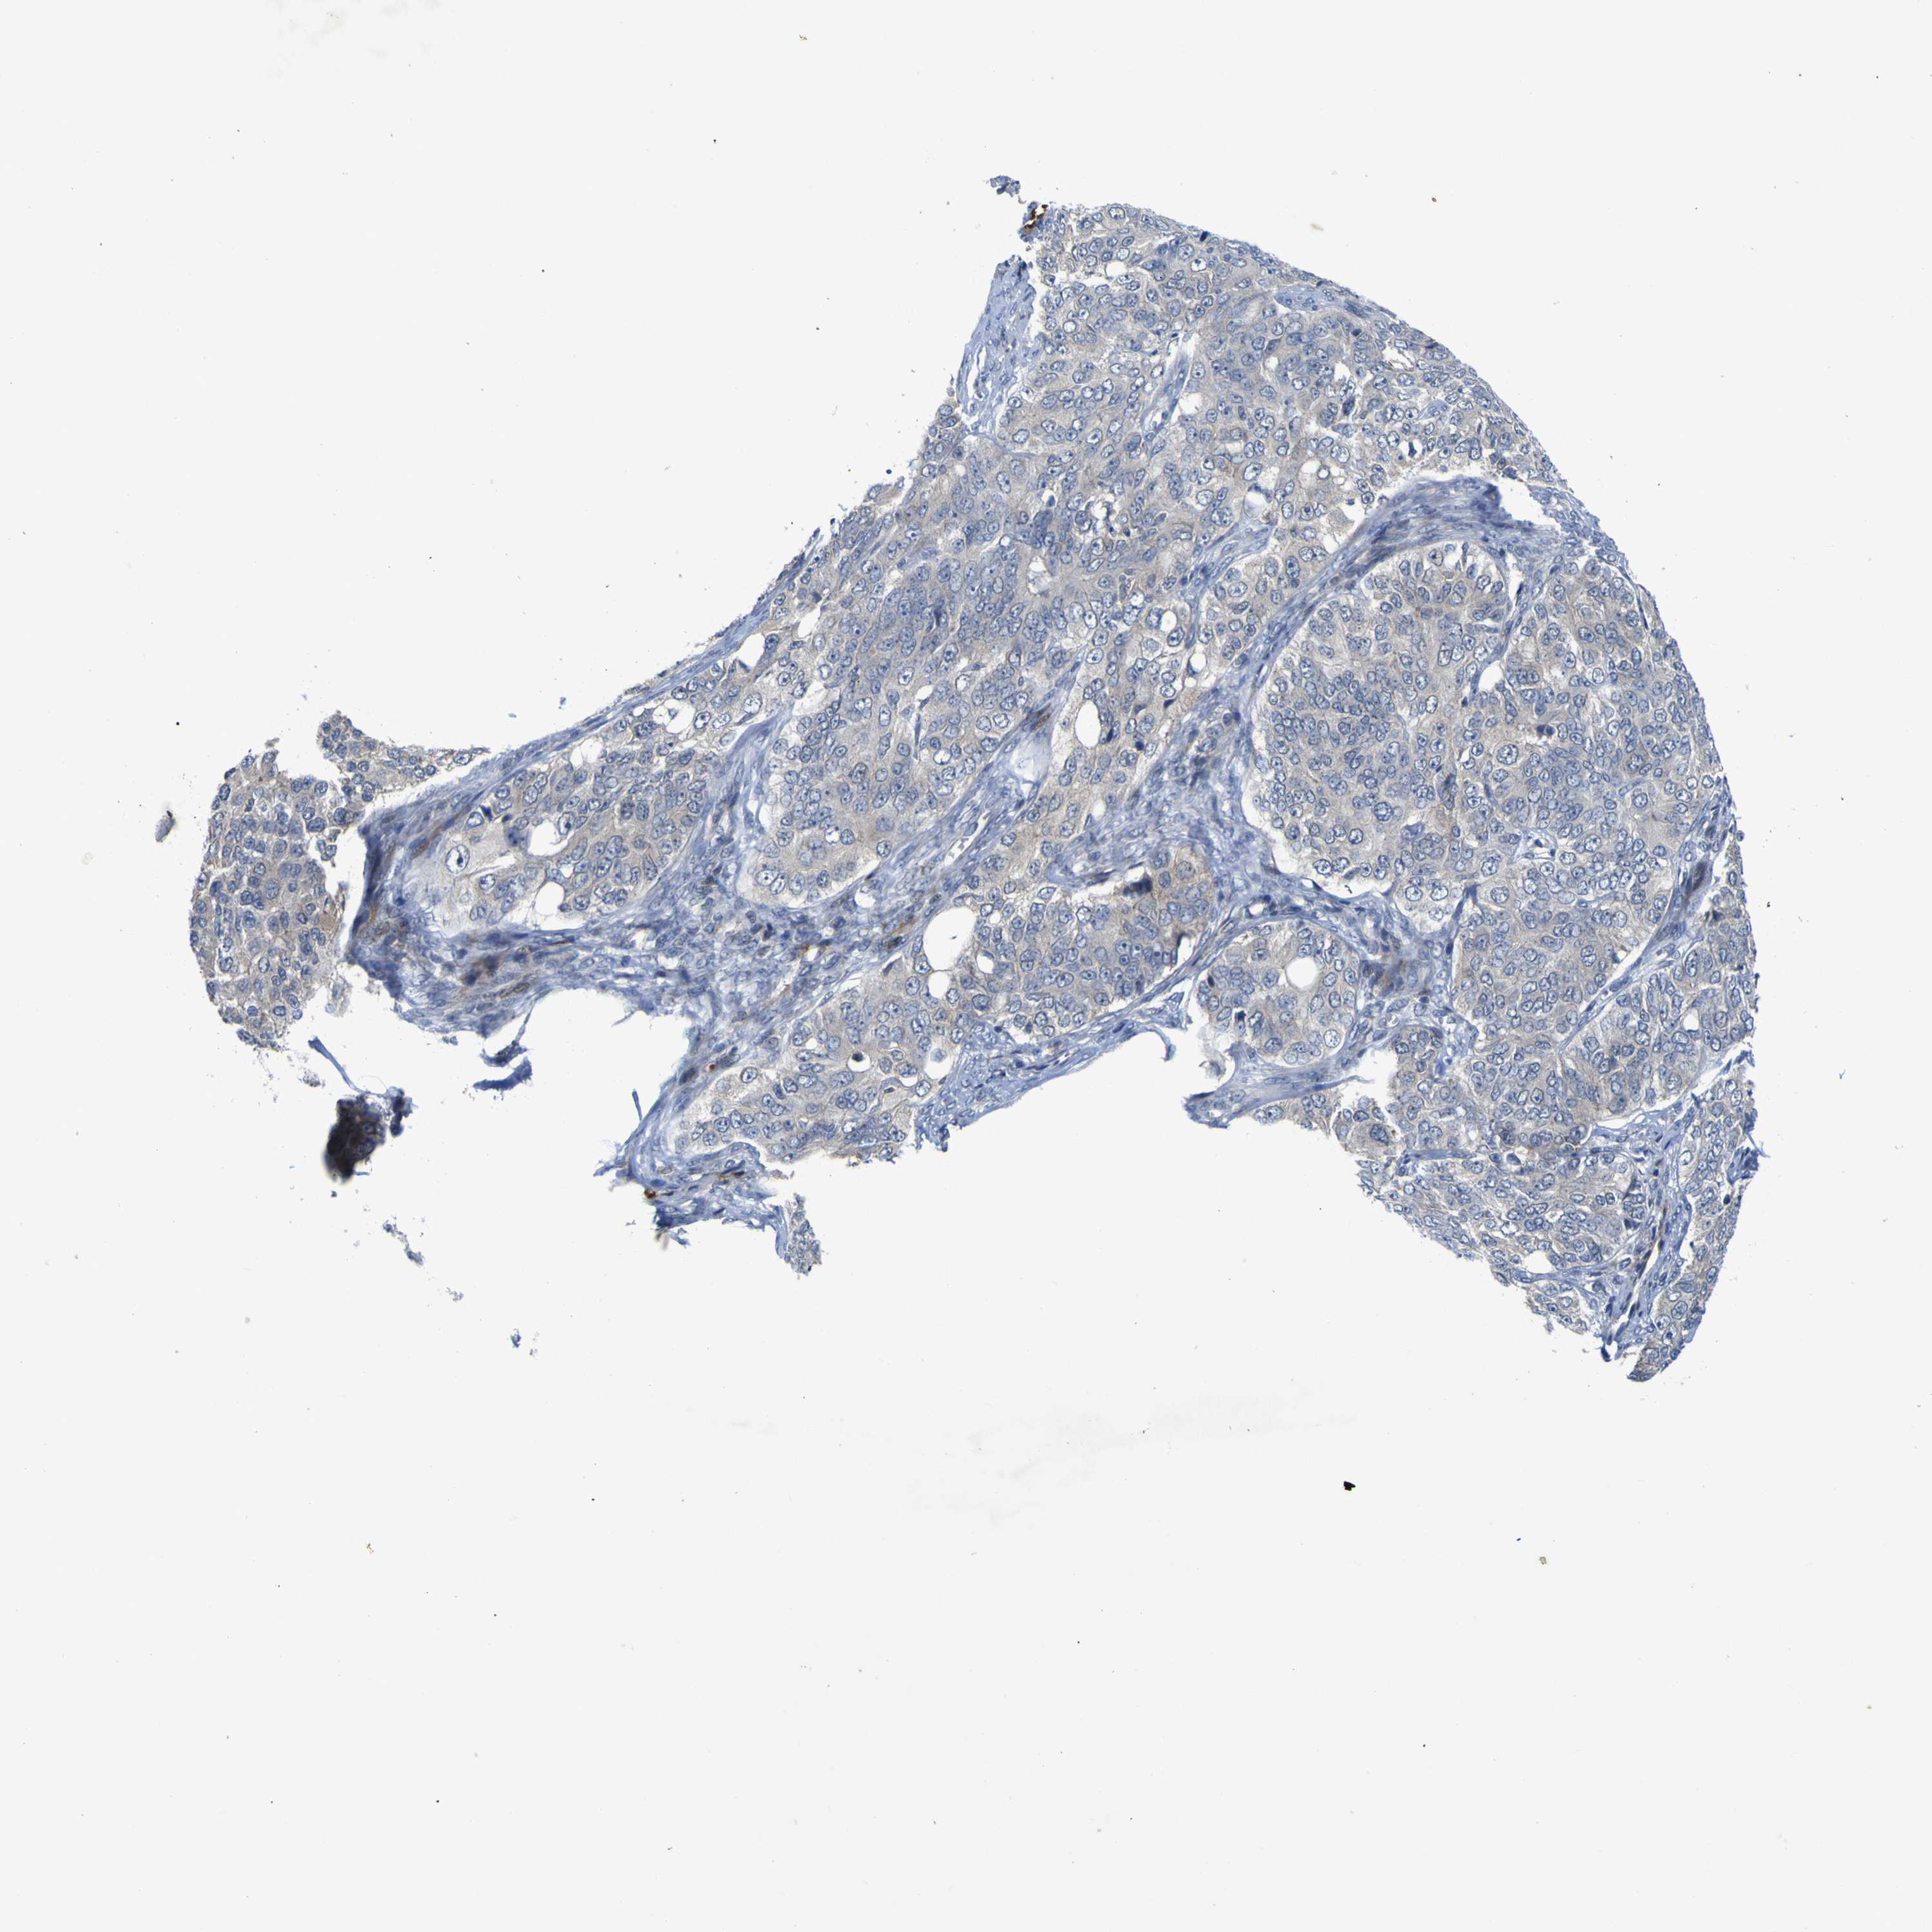

OVARIAN CANCER - Protein expressioni

A mouse-over function shows sample information and annotation data. Click on an image to view it in a full screen mode. Samples can be filtered based on level of antibody staining by selecting one or several of the following categories: high, medium, low and not detected. The assay and annotation is described here.

Note that samples used for immunohistochemistry by the Human Protein Atlas do not correspond to samples in the TCGA dataset.

Antibody stainingi

Antibody staining in the annotated cell types in the current human tissue is reported as not detected, low, medium, or high, based on conventional immunohistochemistry profiling in selected tissues. This score is based on the combination of the staining intensity and fraction of stained cells.

Each image is clickable and will lead to virtual microscopy that enables deeper exploration of all samples and also displays staining intensity scores, fraction scores and subcellular localization as well as patient and tissue information for each sample.

Antibody HPA018127

Antibody HPA027887

Antibody CAB012302

Staining

High

Medium

Low

Not detected

Intensity

Strong

Moderate

Weak

Negative

Quantity

>75%

75%-25%

<25%

None

Location

Nuclear

Cytoplasmic/membranous

Cytoplasmic/membranous,nuclear

Cystadenocarcinoma, serous, NOS

Carcinoma, endometroid

Cystadenocarcinoma, mucinous, NOS

Carcinoma, NOS